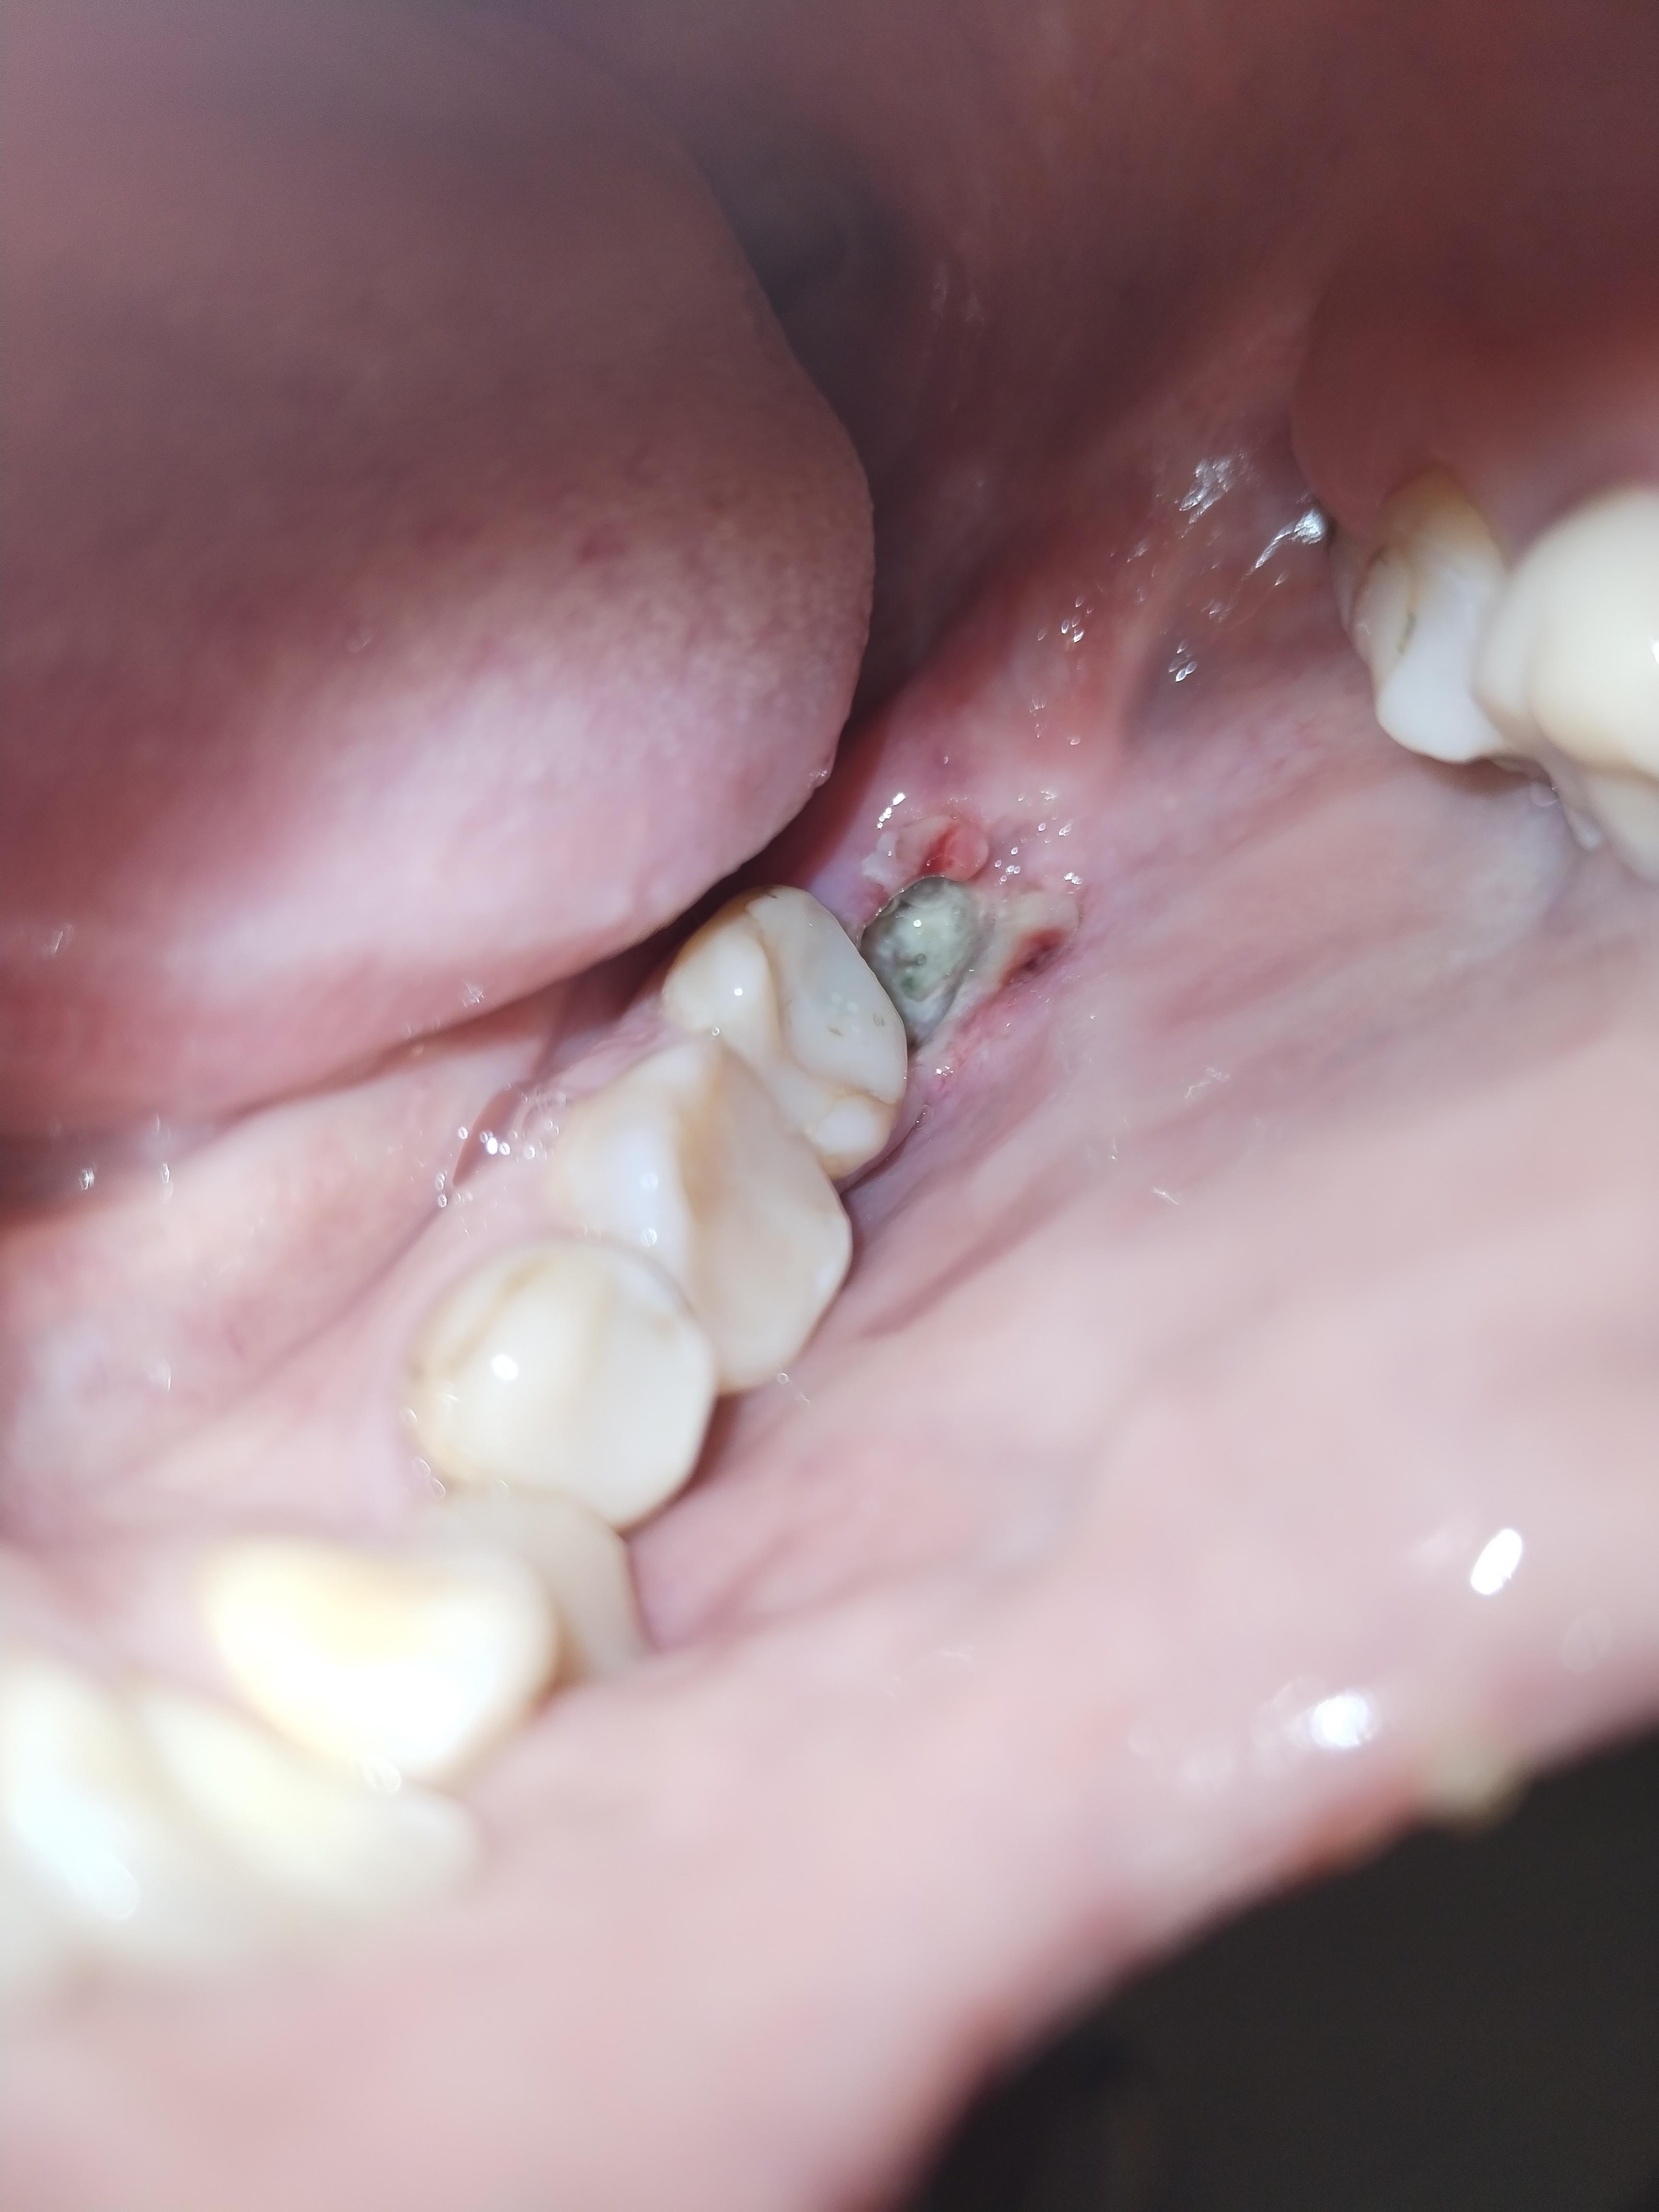

4 дня назад удалили зуб мудрости. Сегодня совершила глупость, когда почувствовала что попал в ранку кусочек огурца решила вмести его ватной палочкой. Теперь ямка стала поглубже, но вроде как белесоватый налёт сохраняется. Боли есть небольшие, но они уменьшаются, и я каждый день пила кетарол, так что не могу судить о том что боль увеличивается или нет. Запаха вроде как никакого нет.

Покажитесь своему хирургу. На 4-ый день после удаления боли быть не должно. И необходимости пить обезболивающий препарат тоже не должно быть. У вас (судя по фото) разрушился сгусток в лунке, протекает альвеолит. Чтобы не усугубить состояние, нужно местное лечение. Это может сделать ваш лечащий врач.